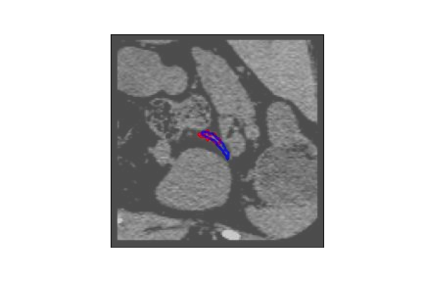

The human annotations are imperfect, especially when produced by junior practitioners. Multi-expert consensus is usually regarded as golden standard, while this annotation protocol is too expensive to implement in many real-world projects. In this study, we propose a method to refine human annotation, named Neural Annotation Refinement (NeAR). It is based on a learnable implicit function, which decodes a latent vector into represented shape. By integrating the appearance as an input of implicit functions, the appearance-aware NeAR fixes the annotation artefacts. Our method is demonstrated on the application of adrenal gland analysis. We first show that the NeAR can repair distorted golden standards on a public adrenal gland segmentation dataset. Besides, we develop a new Adrenal gLand ANalysis (ALAN) dataset with the proposed NeAR, where each case consists of a 3D shape of adrenal gland and its diagnosis label (normal vs. abnormal) assigned by experts. We show that models trained on the shapes repaired by the NeAR can diagnose adrenal glands better than the original ones. The ALAN dataset will be open-source, with 1,594 shapes for adrenal gland diagnosis, which serves as a new benchmark for medical shape analysis. Code and dataset are available at https://github.com/M3DV/NeAR.